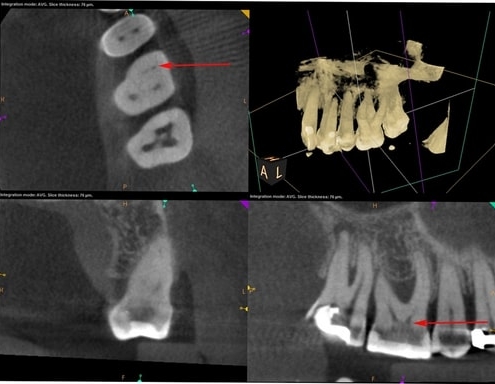

Tehnike pronalaska sekundarnog meziobukalnog kanala

Oblik obrisa pristupnog kaviteta prvog gornjeg kutnjaka trokutast je i smješten u mezijalnoj polovici zuba s osnovom prema bukalno i vrhom prema lingvalno (Slika 3.). Meziobukalni korijen vrlo je širok u bukolingvalnom smjeru, tako da je česta pojava manjeg sekundarnog meziobukalnog kanala. [8] Dno pulpne komore ima određena morfološka obilježja koja su od velike pomoći pri traženju kanala. Obično su na dnu vidljive linije koje vode prema ulazima u kanale i tvore zamišljenu „mapu“, odnosno rostrum canalis. [1] Primarni meziobukalni kanal smješten je blago distalno u odnosu na vrh meziobukalne kvržice, dok je manji sekundarni meziobukalni kanal smješten mezijalno od zamišljene linije koja povezuje primarni meziobukalni i palatinalni kanal, približno na udaljenosti 1 do 3 mm od primarnog. [4] Sam ulaz u sekundarni meziobukalni kanal teško je uočljiv kliničkom inspekcijom zbog dentinskog ramena koje ga pokriva i koje je potrebno ukloniti za lakši pristup kanalu. Osim dentinskog ramena, problem je i meziobukalni nagib ulaza te nagla zavijenost kanala u koronarnoj trećini prema mezijalno što ukazuje na najjednostavniji pristup iz distopalatinalnog kuta. [10] Upravo iz navedenih razloga, kako bi se poboljšala sama pristupačnost kanalu, potrebna je početna priprema i modifikacija pristupnog kaviteta u romboidni oblik uz oprez i minimalnu invazivnost. Istraživanjem je dokazano da je uklanjanje dentina s dna pulpne komore (tzv. troughing) do 2 mm od palatinalnog prema primarnom meziobukalnom kanalu korisna metoda te da su njezine prednosti nadmašile rizik od perforacije. [1] Potrebna je i dobra vizualizacija dna pulpne komore za što se koristi mikroskop, lupe ili barem intraoralno ogledalo s prednjom reflektirajućom površinom. Uz dobru pristupačnost i vizualizaciju lakše je istraživanje dna pulpne komore i traženje ulaza u kanal. Instrumenti poput DG16 Explorer (Slika 4.) ili tanki instrument poput D finder #10 (Slika 5.) od velikog su značaja za lociranje kanala. Iznimno su korisni i ultrazvučni instrumenti koji selektivno uklanjaju kalcifikacije u pulpi i čuvaju dentin od pretjerane štete te otkrivaju skriveni ulaz u kanal. Važno ih je pažljivo koristiti, laganim, kontroliranim pokretima kako bi se izbjeglo pretjerano uklanjanje dentina i iatrogena perforacija. Kod samog traženja kanala, irigacija može pomoći u njihovoj lokalizaciji. Natrijev hipoklorit ima antimikrobna svojstva, osigurava bolju vidljivost, smanjuje rizik od kontaminacije, omogućuje lakši pristup instrumentima te uklanja ostatke organskog materijala. Pulpni ostaci mogu reagirati s natrijevim hipokloritom pri čemu se stvaraju mjehurići, odnosno dolazi do stvaranja kisika, što je pokazatelj položaja ulaza u kanal te potencijalnog postojanja novih, neotkrivenih kanala. Uz natrijev hipoklorit, kao dijagnostičko sredstvo za lociranje kanala upotrebljava se i kemijski spoj 1% natrijev fluorescein. To je oftalmološka otopina koja ima svojstvo vezanja za vezivno tkivo i svijetli kada se izloži plavom svjetlu. Nalapatti i Glassmann predložili su njegovu upotrebu, na način da se otopina aplicira u pulpnu komoru i ostavi da djeluje i reagira 2 minute. [1] Aplikaciju je potrebno obaviti oprezno i paziti na određeni vremenski interval djelovanja, budući da postoji rizik od obojenja zuba. Nakon toga potrebno ju je izložiti plavom polimerizacijskom svjetlu, a kanale promatrati mikroskopom. Važno je obilno isprati pulpnu komoru natrijevim hipokloritom nakon završenog postupka. Na temelju te tehnike, napravljen je i veliki pomak u razvitku mikroskopa, odnosno kobaltno-plavog filtra koji omogućuje još precizniju i jednostavniju primjenu natrijevog fluoresceina. [1] Još jedan vrijedan dijagnostički alat, koji nam omogućuje trodimenzionalan prikaz anatomije jest CBCT (konusna kompjutorizirana tomografija). Ova tehnologija omogućuje bolju vizualizaciju, prepoznavanje varijacija, planiranje samog pristupa, minimalno invazivnu preparaciju te veću predvidivost terapije (Slika 6.). Kliničkom studijom dokazano je da je učinkovitost korištenja CBCT-a u pronalaženju dodatnih sekundarnih meziobukalnih kanala u maksilarnim kutnjacima ograničena te je sam kanal bio prikazan u 33 % slučajeva. [11]